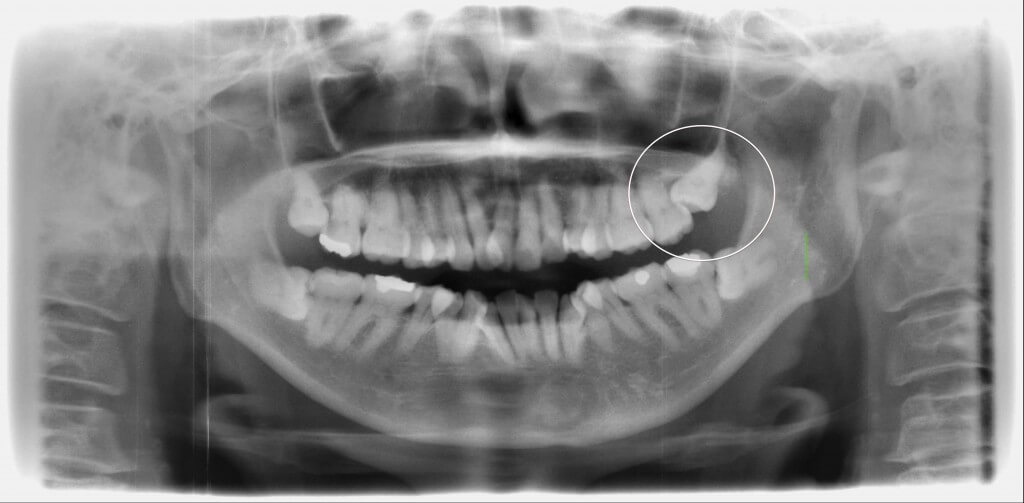

Case.5

上顎の埋伏智歯を抜歯した症例です。前方歯に引っかかった状態のため歯冠の分割後に抜歯を行いました。